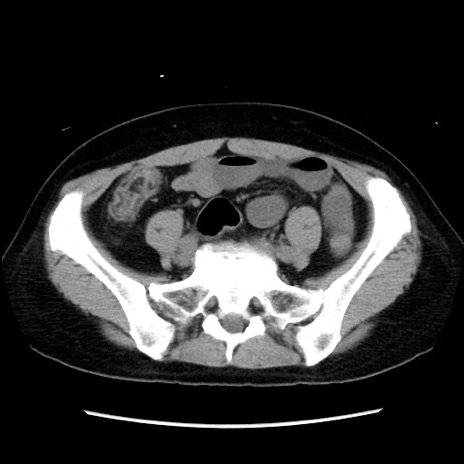

症例10(横断像)

【症例】 50歳代女性

【主訴】 腹痛

【現病歴】前日生レバーを食べた。今朝に排便あり。 昼前に突然発症の腹痛を生じ、当院救急外来を受診した。

【既往歴】 子宮筋腫にてで子宮全摘後

【身体所見】 意識清明、腹部:平坦、軟、下腹部やや左を中心に圧痛・反跳痛あり、筋性防御あり

【データ】WBC 7800、CRP 0.07